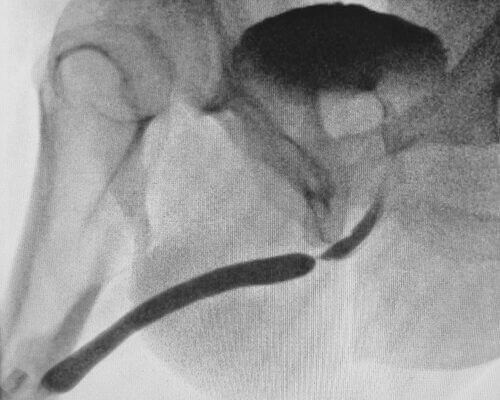

Striktura sečnice (striktura uretre) oz. zožitev sečnice je bolezen, ki jo označuje ožanje sečnice - sečnega kanala. Posledica tega je težavno uriniranje in težavno praznjenje sečnega mehurja.

Striktura sečnice in težavno praznjenje sečnega mehurja dolgoročno vodi v resnejše težave kot so na primer uroinfekti, disfunkcijonalno delovanje sečnega mehurja, sečni kamni, ledvična okvara in nenazadnje popolna zapora odvajanja urina.

Endoskopska uretrotomija (uretrotomia interna - notranje prerezanje zožitve sečnice) je kirurški poseg pri katarem pod kontrolo kamere vstopimo v sečnico z endoskopom in prerežemo zožitev sečnice na več mestih cirkularno z namenom razširitve sečničnega kanala.

Poseg je metoda izbora zdravljenja ob strikturah sečnice, ki so krajše od enega centimetra in ob odsotnosti spongiofibroze.